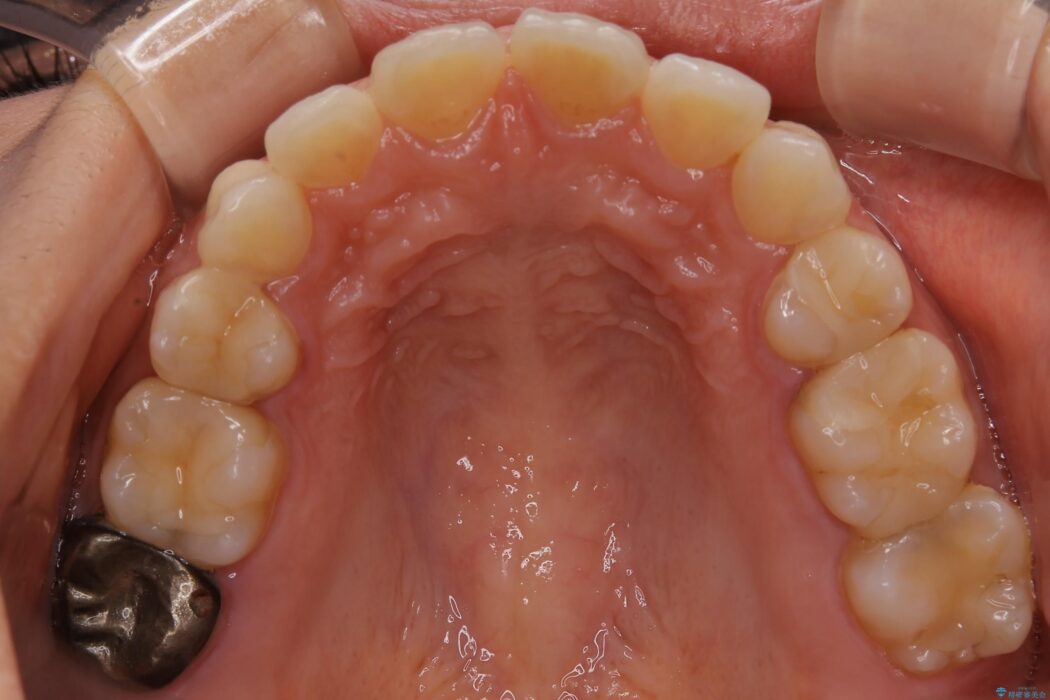

【20代女性】矯正治療後の後戻り

- 患者様:20代女性

- 治療期間:1年

- 矯正装置:審美装置

- 概算治療費:66万円

抜歯矯正後の後戻りについてご相談にいらした患者様です、